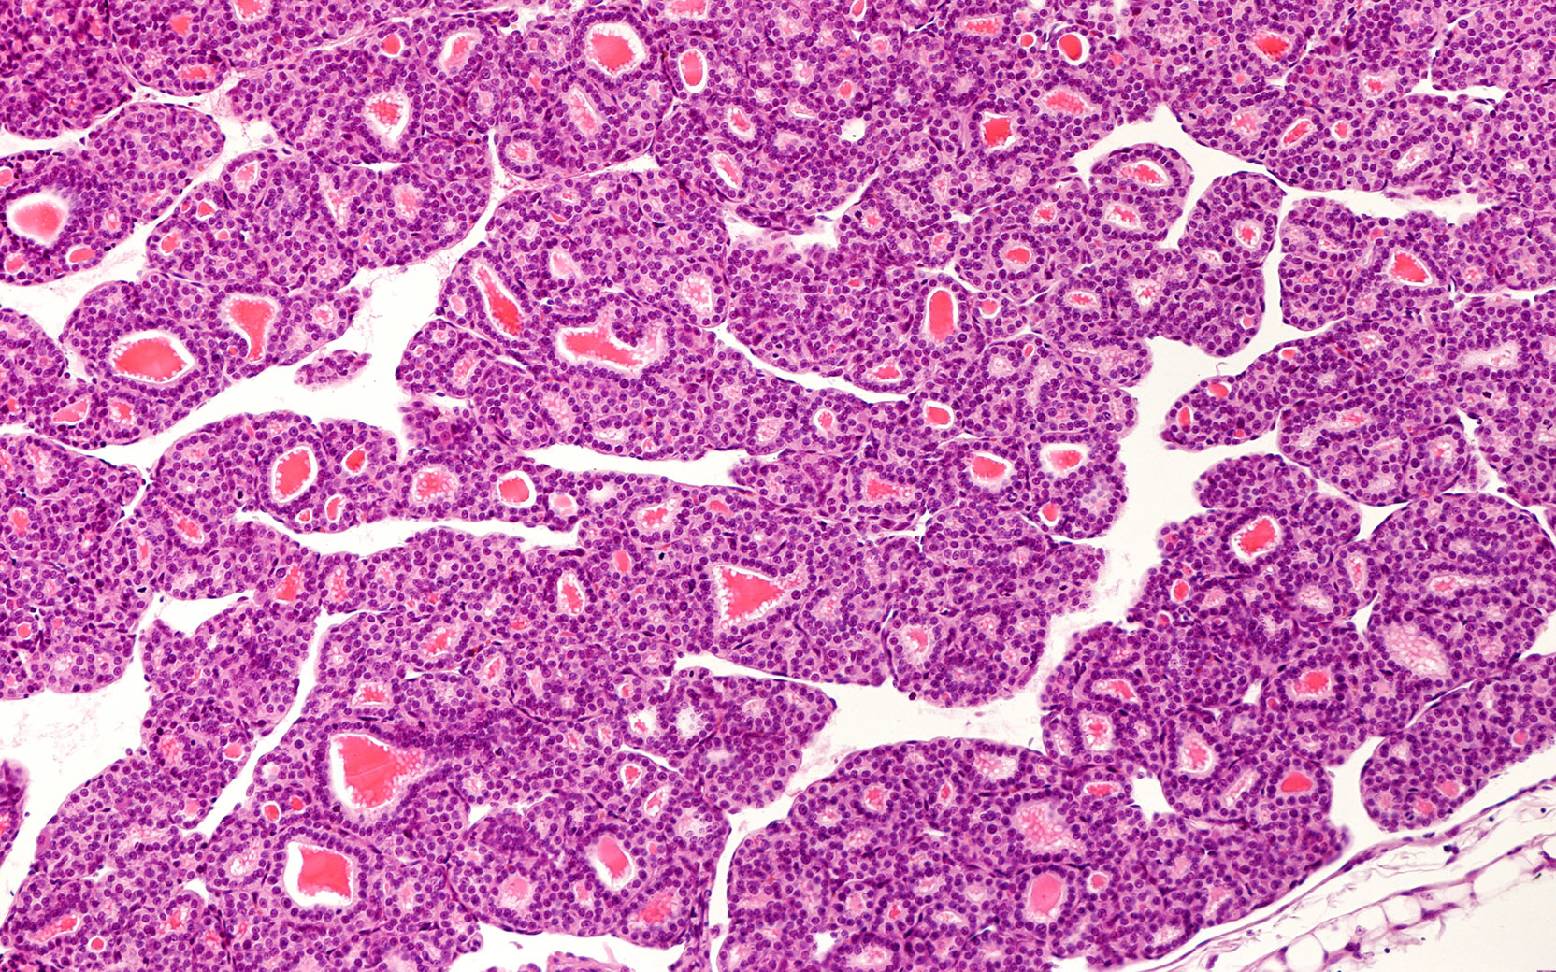

In der Mehrzahl der Fälle sind gutartige Tumoren Ursache der Vergrößerung der Schilddrüse und damit Auslöser für die hormonelle Entgleisung. Nur in sehr seltenen Fällen stecken bösartige Tumore dahinter. Aufgrund der Zellvermehrung kommt es zu einer exzessiven Ausschüttung bestimmter Schilddrüsenhormone. Da diese Hormone viele verschiedene Aufgaben im Kohlenhydrat-, Fett- und Eiweißstoffwechsel, aber auch im Nervensystem übernehmen, können die Auswirkungen sehr vielschichtig sein.